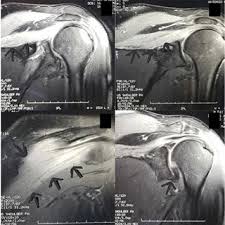

Parsonage-Turner syndrome also known as acute idiopathic brachial neuritis is a painful nontraumatic disorder involving the shoulder girdle. Este paciente presentaba cambios de denervación muscular en los músculo subescapular figura arriba izquierda T2 FS deltoides y supraespinoso figura derecha T2 FS y del infraespinoso figura abajo izquierda T2. In some cases the pain may extend to the neck lower arm andor hand on the affected side.

On MRI muscles around the shoulder can show features of denervation. To review retrospectively the magnetic resonance MR imaging findings and clinical information of patients with Parsonage-Turner syndrome PTS. Parsonage Turner syndrome is usually characterized by the sudden onset of severe pain in the shoulder and upper arm which is often described as sharp aching burning stabbing or throbbing.

Parsonage Turner Syndrome Radsource